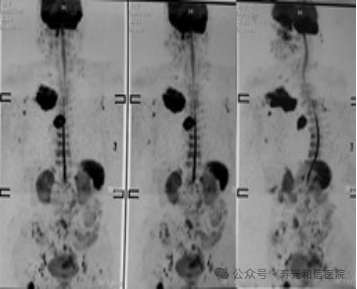

3. 全身评估,一“扫”多查。

一次检查可同时观察头颈部动脉主干及分支,结合平扫还能评估周围脑组织是否受损(如缺血灶),适合筛查脑卒中或复杂血管病变。

4. 动态血流信息,辅助治疗决策。